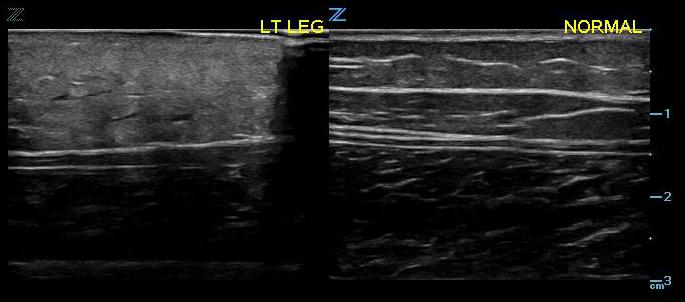

- Figure 1. Normal skin, subcutaneous tissue, and fascia.8

- With the equipment typically used for bedside ultrasonography, the epidermis and dermis cannot be differentiated. They appear together as a thin, hyperechoic layer.8

- The subcutaneous layer appears hypoechoic on ultrasound, with two components: hypoechoic fat interspersed with hyperechoic linear echoes running mostly parallel to the skin, which represent connective tissue septa.

- Veins and nerves can be visualized within the subcutaneous layer.

- Fascia appears as a linear hyperechoic layer. Its thickness will vary depending on the location.